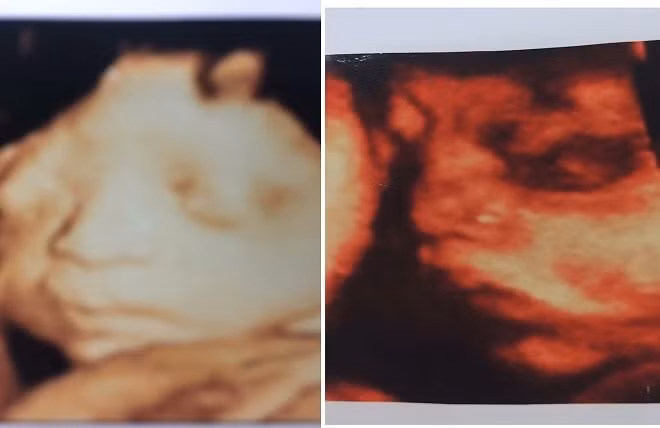

Thông tin từ phía gia đình người mẹ có song thai bị chết lưu thì hiện tại chị đang có những dấu hiệu trầm cảm sau rất nhiều áp lực.

Liên quan tới sự việc gia đình anh Nguyễn Ngọc L. (phường Dĩnh Kế, TP.Bắc Giang, tỉnh Bắc Giang) có đơn gửi UBND phường Dĩnh Kế và UBND xã Tân Thịnh (huyện Lạng Giang, tỉnh Bắc Giang) với mong muốn cơ quan chức năng vào cuộc làm rõ vấn đề về thai nhi mất tích bí ẩn và mang con anh L. về chôn cất, PV đã có cuộc trao đổi với mẹ đẻ của anh L.

Mẹ chị M. cho hay, hiện tại sức khỏe của chị rất yếu, tâm lý bất ổn. Bác sĩ cũng khuyến cáo không nên để chị M. kích động và cần giữ cho M. bình tĩnh.

Chồng quẫn trí tự tử vì mất 2 con ở Bắc Giang, bạn thân đi cùng vợ cho biết thai nhi bị chết lưu khoảng 2 tuần trước khi người vợ thông báo mất con

Người vợ đang bị trầm cảm?